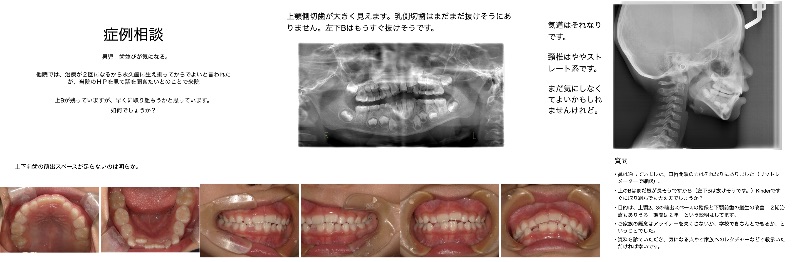

Q

N様10代Ⅲ級です。 予定ではスマーティー予定です。どのシリーズがよいでしょうか?

口蓋縫合を意識して矯正を介入した場合 外科の可能性もお伝えしたほうが良いですかね